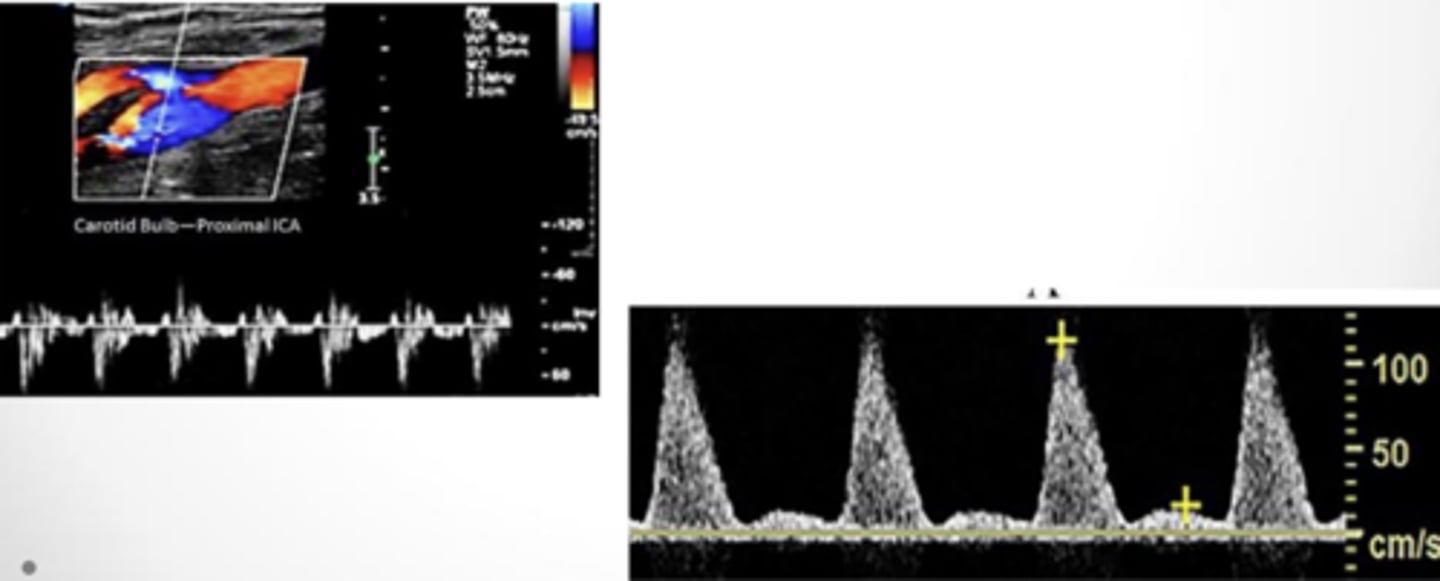

Disturbed/Flow Separation

-flow lines are slightly disrupted

-bulb, bifurcation, noncritcal stenosis

Flow Jet

-maximum flow velocities across a narrowed segment

-velocity is correlated to the percentage of narrowing

-tightly narrowed segment = high velocities

Occluded Flow

no flow present due to occlusion of artery